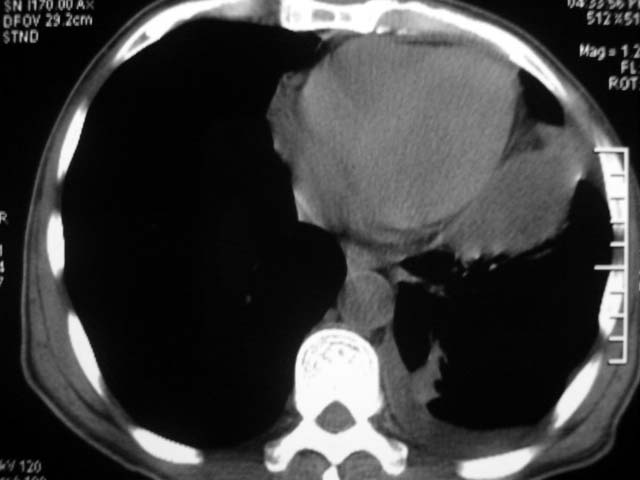

男,52岁,发热2月,糖尿病史。

抗结核治疗irpz方案,血糖未治疗,空腹15.9左右。症状无好转,左胸痛。

复查ct

结果:两肺继发性肺结核并曲霉菌感染。